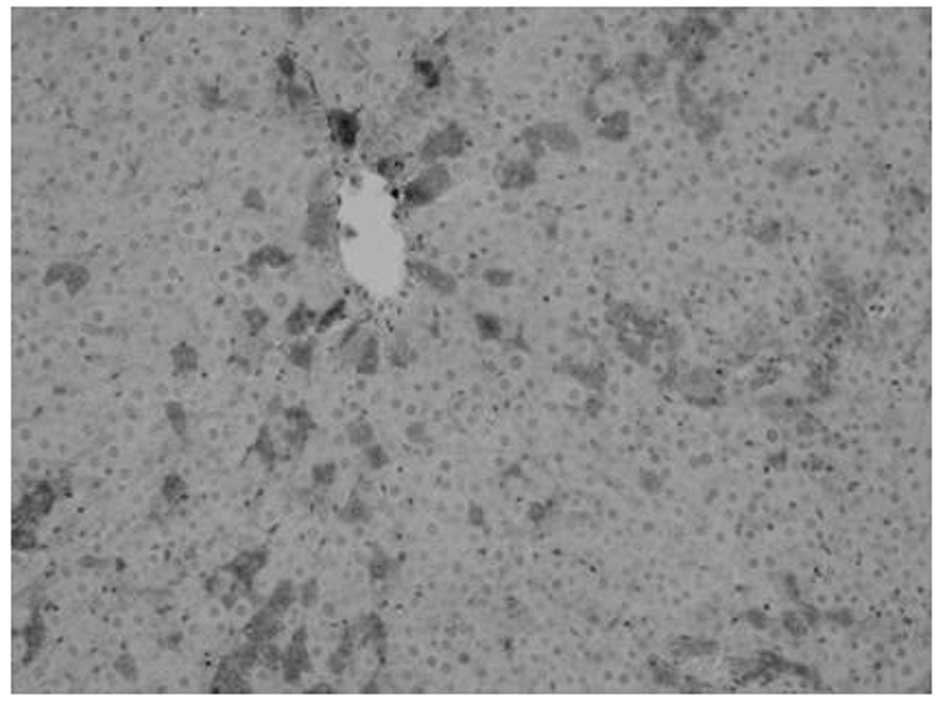

Proliferation of oval cells

Oval cells were found in the ductular area on day 1 following PH. Compared with mature hepatocytes, oval cells were observed to exhibit reduced volume, higher ratios of nucleus to cytoplasm, round- or oval-shaped nuclei and antibody OV6 expression. The number of oval cells increased with time. OV6-expressing cells were found to be distributed along the ductular to the parenchymal regions of the liver on days 3–7. Cell numbers peaked at day 7 and then decreased. A marked decrease was noted at day 14 following surgery, however, OV6-expressing cells were noted only in the ductular region. Compared with model, fewer OV6-expressing cells were identified in the matrine group (Figs. 2–5 and Table III).

Figure 2

Expression of OV6 in liver tissue of model group at day 3 following partial hepatectomy (magnification, ×200).